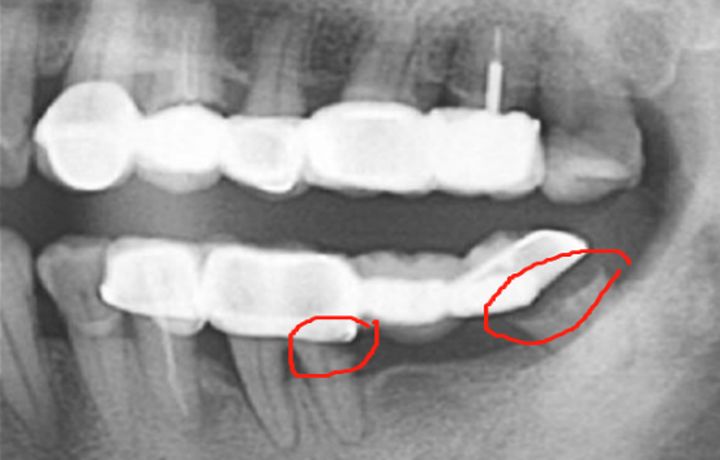

(下颌四个单位的联冠,红圈处基牙龋坏)

一损俱损,多颗基牙连在一起组成的联冠,一旦其中一颗牙齿出现了问题,那这一排烤瓷牙可能都会跟着遭殃,面临着被拆除的风险。

常见的单冠,和缺一颗牙齿使用的三联冠最常用 ,风险最小,四个及四个以上的联冠,慎重去做,大跨度的跨江联桥(5、6颗及以上)修复,要评估好风险,权衡利弊后再做决定,别轻易就让医生把牙齿磨了。